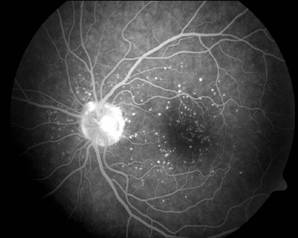

Simptomatologia obiectiva:

modificarile patologice intereseaza toate structurile oculare. Pe masura ce leziunile degenerative progreseaza, apare o scadere a acuitatii vizuale, progresiva.

Complicatii: cataracta complicata, 1 uxatia cristalinului, dezlipirea de

retina. Miopia degenerativa se poate asocia cu malformatii genetice ale segmentului anterior al ochiului (colobom irian, glaucom congenital tardiv) sau al segmentului posterior al ochiului (degeneresceniie tapeto-retiniene, hemeralopia congenitala). Asociatia miopiei cu glaucomul cu unghi deschis